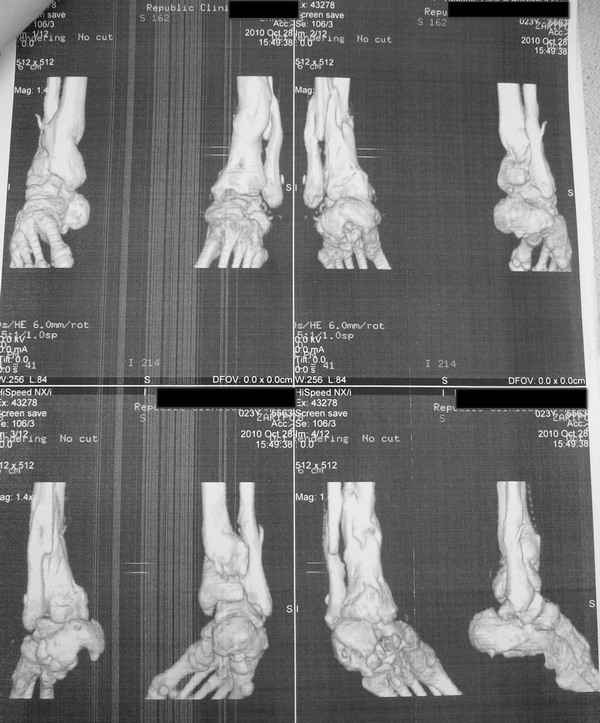

Молодая девушка со сросшимися многооскольчатыми переломами пяток и голеней.Young girl with fractures of the calcaneus Больная Н., 25 лет, падение с высоты (2008 г.). Жалобы на боли в области голеностопных суставах, в области пяток при ходьбе. Лечилась в аппаратах внешней фиксации по поводу открытых оскольчатых переломов обеих голеней, переломов пяток. Далее по поводу несросшихся переломов голеней –ЧКОС аппаратами внешней фиксации. Переломы срослись, аппараты демонтированы весной 2010г. В левой пяточной области в месте проведения спицы имеется сукровичное отделяемое. При ревизии гноя нет. Чем помочь девушке?

Patient N., age 25, falls from heights (2008). Complaints of pain in the ankles, in the heel when walking. She was treated by external fixation on open comminuted fractures of both legs, fractures of the calcaneus. Then she was treated by external fixation from nonunion of both legs. Now fractures are fused, apparatuses removed in the spring of 2010. How to help a girl?